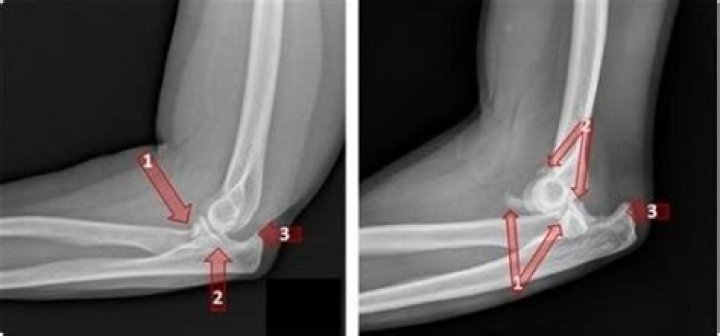

What are some elbow injuries?

The most common elbow injuries seen by orthopedists and surgeons include the following:

• Tennis elbow (medical term: lateral epicondylitis).

• Flexor Tendinitis.

• Ulnar Collateral Ligament (UCL) Injury.

• Valgus Extension Overload (VEO).

• Olecranon Stress Fracture.

• Ulnar Neuritis.